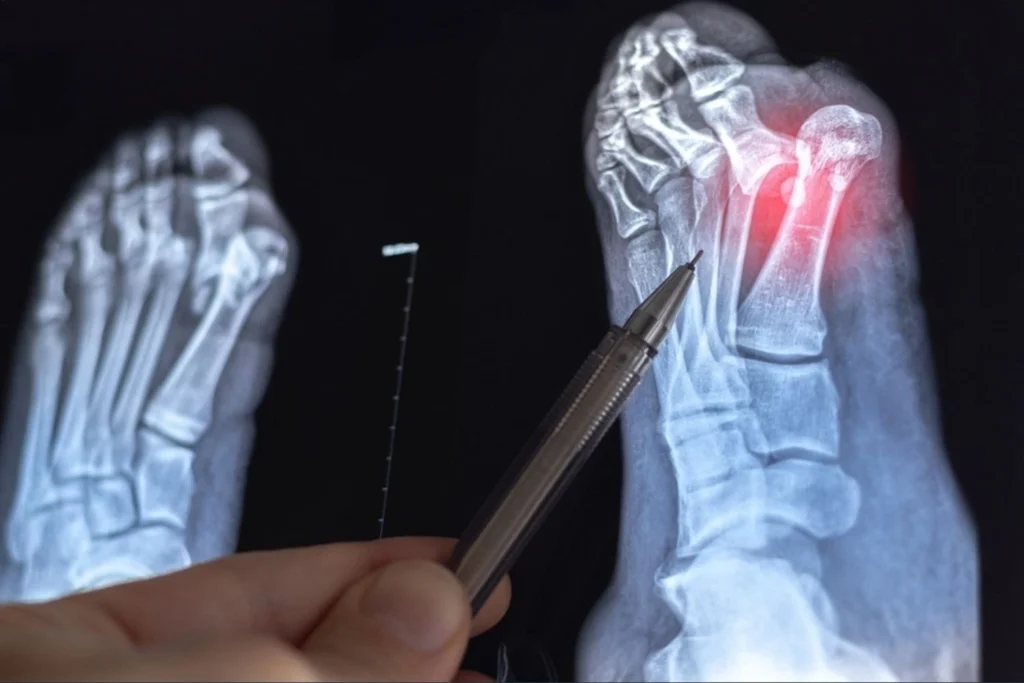

A bunionectomy is a surgical procedure that corrects a bunion by realigning the joint at the base of the big toe. Surgeons remove the bony bump and restore proper alignment of the toe.

Doctors usually recommend surgery when bunions cause severe pain, difficulty walking, or fail to improve with conservative treatment.